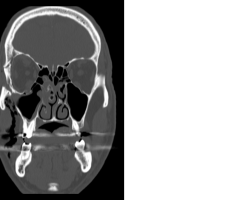

- TDM sans injection en coupes axiales, coronale et sagittale

Fracture du plancher orbitaire, du toit de l’orbite, de la paroi temporale. - Photos